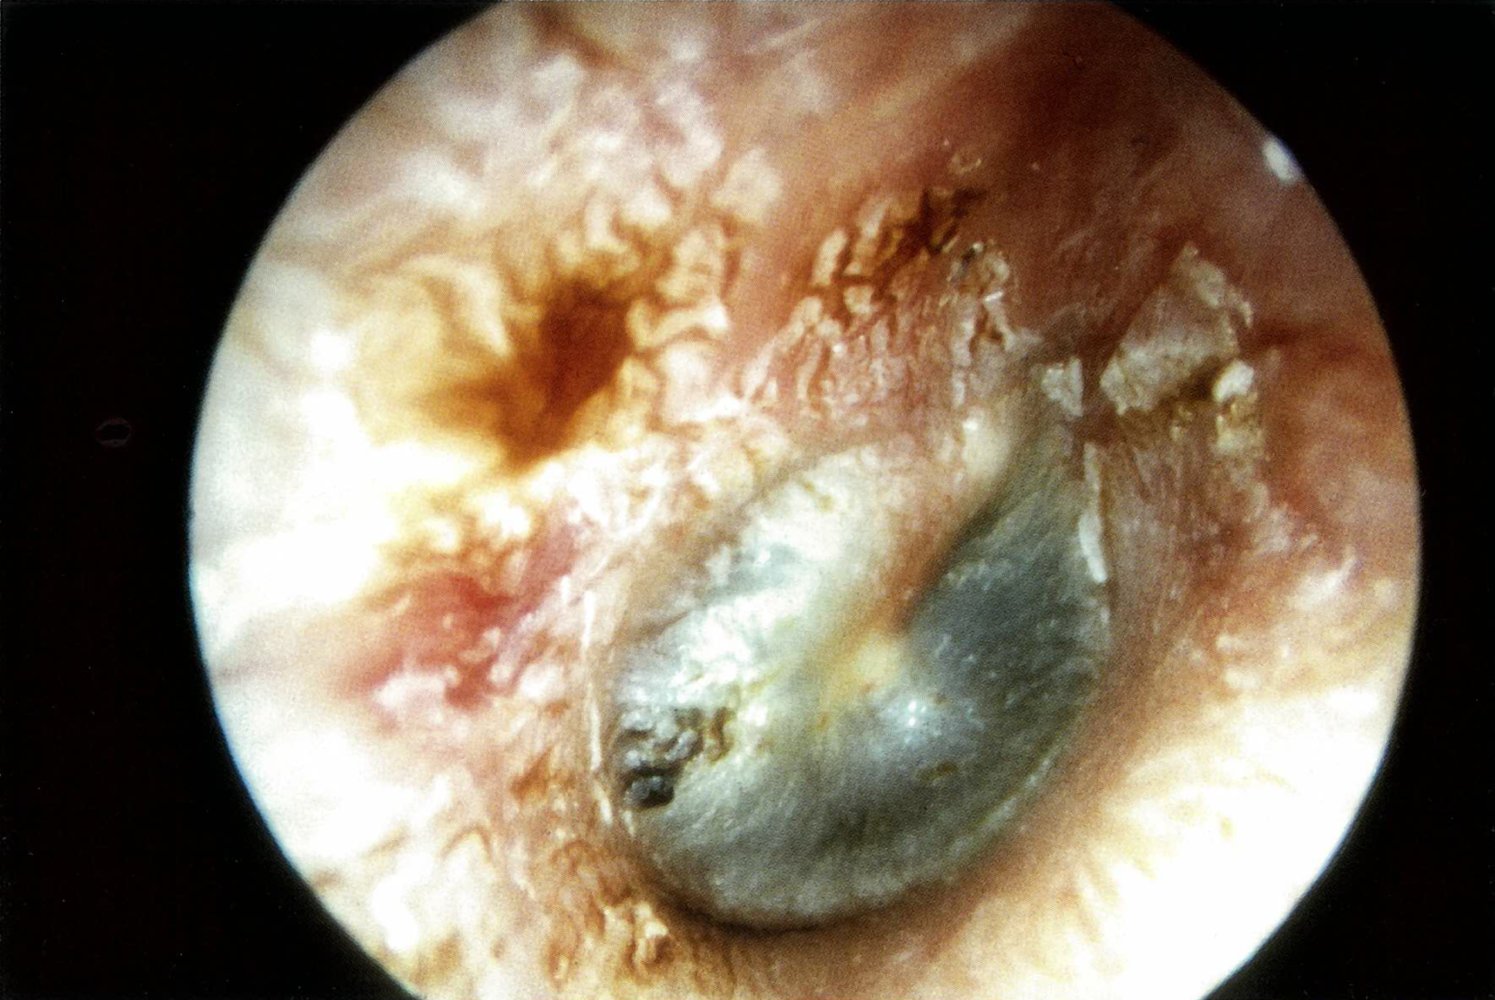

Laryngoscopy or bronchoscopy